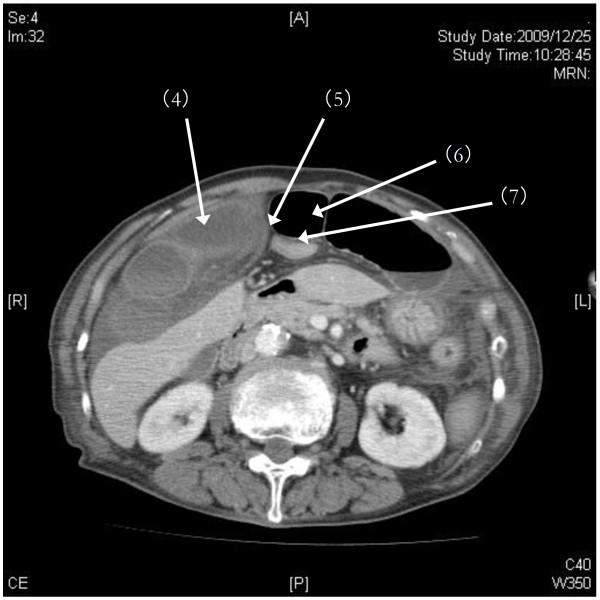

A 77-year-old Japanese woman presented to our emergency department with sudden hematemesis, occurring at least four to five times over a 12-hour period. No ulcer or gastrointestinal bleeding was detected on gastroendoscopy. A 40mm mass in the inferior lobe of the right lung was found on a chest X-ray, and our patient's symptoms were therefore initially ascribed to aspirated blood from lung tumor-associated hemoptysis. However, our patient continued to show signs of severe abdominal pain and decreased urine output despite aggressive hydration, leading her examining physicians to search for a possibly severe, occult abdominal pathology. On emergent computed tomography imaging, we found an acute strangulated internal hernia within the falciform ligament. Diagnosis was made by helical computed tomography, permitting rapid surgical intervention.

Our findings on computed tomography imaging assisted with the pre-operative diagnosis and enabled us to make a rapid surgical intervention. Early diagnosis may help preclude significant strangulation with unnecessary resection.